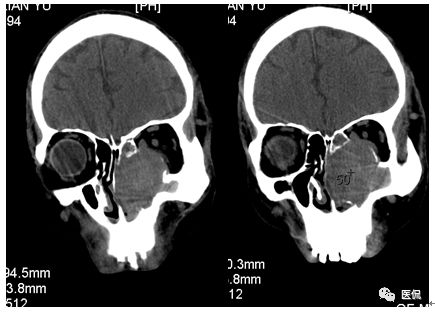

冠状位平扫

CT平扫及增强示:左侧上颌窦及鼻腔可见软组织密度影,呈膨胀性生长,周围骨质压迫性吸收破坏,累及左眶,病灶密度不均匀,周边区可见点状钙化,增动脉期轻度强化,局部见小灶性稍高密度区,静脉期病灶内见不均匀明显强化,CT值最高达117HU,延迟期强化范围有所增大。

本例病灶较大,周围骨质可见吸收破坏,并累及眼眶,病灶内少量钙化,增强扫描具有一定特征性,表现为动脉期轻度强化,局部见小灶性稍高密度区,静脉期病灶局部呈明显强化,CT值最高达117HU,延迟期强化范围有所增大,呈延迟渐进性强化的特点,推测为病灶内出血所致。